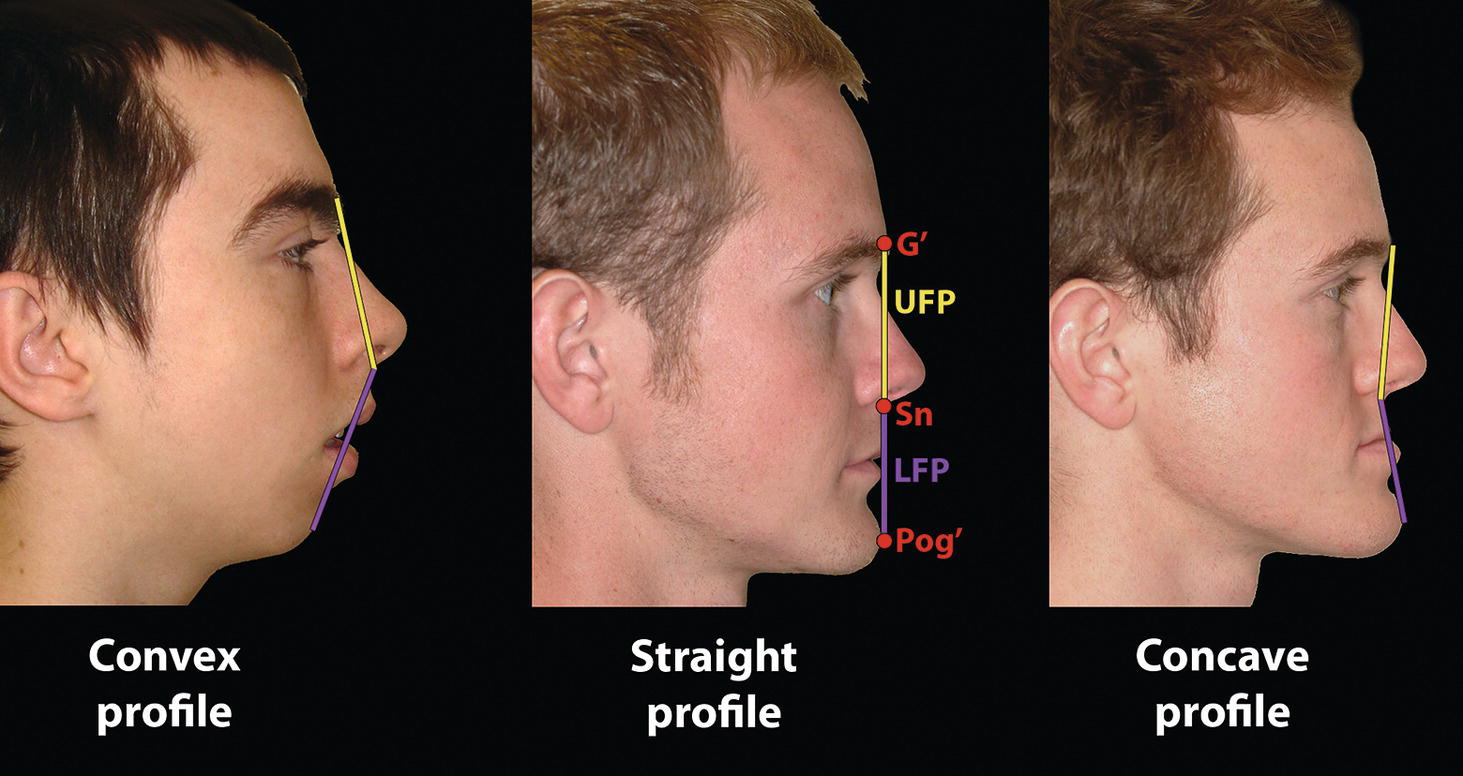

‘It is the common wonder of all men, how among so many millions of faces, there should be none alike’. Sir Thomas Browne (1605–82), English physician and writer, Religio Medici (1643)1 Individual variability is a fundamental principle in human biology. One of the most variable and distinguishable parts of the human body is the craniofacial complex. Clinicians will often compare a patient’s craniofacial measurements and proportions to the so‐called population norms (normative values) or even to classical ideals. However, Simon (1926) stated: ‘all we ever find are variations; an exact, ideal normal does not exist, cannot exist. And this is our enigma; in theory we will never find the normal, in practice we forever feel its need and apply it constantly’.2 The use of population norms may be logically enhanced by evaluating normal ranges of variability. Therefore, clinicians must have a thorough understanding of the normal ranges of variability in every aspect of craniofacial form, depending on age, sex and ethnic variability. Developmental disorders, as well as traumatic injuries and pathological conditions, may lead to deformities of the head and the face. Therefore, clinicians need to have a thorough understanding of the normal anatomy and morphological range of variation of the craniofacial complex in both males and females of different ages and ethnic groups, to act as guidelines when treatment planning the restoration of normal craniofacial proportions. Classifications that are useful for descriptive purposes include: A proportion index provides a numerical expression of the proportionality of a region of the craniofacial complex. The use of proportion indices dates back through the history of craniometry, particularly in the late nineteenth century. Linear (chord) or surface (arc) distances of the skull were measured between a variety of defined craniofacial landmarks; with any two measurements, the smaller was expressed as a percentage of the larger in order to provide a proportion index value. These could be used to provide an indication of skull shape. Figure 8.1 Determination of the normality or abnormality of any craniofacial measurement (or proportion index value) obtained from patients may be evaluated by comparison with the normative values obtained from a normal (average representative) population sample. The normal range of measurements is provided by the mean ±2 standard deviations (SD). The shape of the normal distribution curve shown is determined by the population standard deviation. Craniofacial parameters with small SDs have narrow, taller curves and those with large SDs have broader, flatter curves. Approximately 68% of all values fall within the range of ±1 SD from the mean and 95% within the range of ±2 SD from the mean. The normal range of variability for any craniofacial parameter is taken as being equal to the mean ±2 SDs. Greater differences may be perceived as deformities of gradually increasing severity. The leading researcher in the field of craniofacial anthropometry from the mid‐1960s to the early 2000s was Leslie Farkas, from the University of Toronto. Farkas et al. collected a large quantity of highly relevant anthropometric data between 1968 and 1984, from 2564 individuals.3 These data were used to provide 166 individual facial ratios, presented as proportion indices. In the creation of an index, the smaller measurement is multiplied by 100 (numerator) and divided by the larger measurement (denominator). Thus, a proportion index involves two linear craniofacial anthropometric measurements, with the smaller being expressed as a percentage of the larger. Proportion indices permit objective, quantitative assessment of facial morphology and proportions. Farkas3 identified two basic categories of proportion indices: Each proportion index will have a mean index value and a range of variation for a given population group, based on age, sex and ethnicity. The standard deviation (SD) determines the normal (average) range of variability of an index, from 2 SD below to 2 SD above the mean. Index values within this normal range are regarded as variations of normal proportions.4 Measurements within ±1 SD of the mean are regarded as optimal. The relationship between two measurements is disproportionate if the proportion index value is outside the normal range (Figure 8.1).4 For a number of facial parameters, single morphological measurements or proportion index values may have a large SD and, therefore, wide normal ranges of variation; as such, only measurements or proportion index values which differ considerably from the mean of the population will be perceived as deformities. Conversely, other facial parameters may have very small normal ranges of variability, in which case even a small difference from the mean may be perceived as a deformity. The cephalic index (index cephalicus) is a numerical expression of the ratio between the head width (biparietal diameter) and head length (fronto‐occipital diameter) of a living person. The cephalic index (CI) is calculated by the formula (Figure 8.2): Figure 8.2 Cephalic index. Where: The cephalic index is used in anthropometry to classify head types as (Table 8.1; Figure 8.3): Table 8.1 Classification of anatomical head types Index values according to Martin and Saller.5 Figure 8.3 Head types. The highest cephalic index values occur in the Chinese and the lowest values in African Americans. The larger index values of the Chinese differ significantly from those of whites or blacks (Table 8.2).6 A comparison of the cephalic index values of three ethnic groups was undertaken; North American Caucasians, northern European (German) and eastern European (Czech). The index values indicated a mesocephalic head type for both sexes of North American Caucasians and northern Europeans; and a brachycephalic (short‐wide) head type for the eastern Europeans.6 The head circumference is measured in the horizontal plane around the head, through the glabella and opisthocranion. However, it may be measured across ophyron (the point ‘On’, in the mid‐sagittal plane, of a line tangent to the upper limits of the eyebrows) rather than glabella in order to eliminate the effect of development of the frontal sinuses and superior orbital rims on head circumference.5,7 African Americans have the largest and the Chinese have the smallest head circumference for both sexes. The head circumference is slightly larger for blacks than for whites for both sexes.6 The initial step in facial analysis involves the examination of the face in frontal view in order to assess the overall facial shape. The variety of facial shapes is almost limitless. However, a simple assessment will allow an overall categorization of the basic facial shape. The basic facial shape in frontal view may be any combination of the following: Table 8.2 Cephalic index of three ethnic groups Data modified from Farkas.6 SD = standard deviation. Table 8.3 Head circumference of three ethnic groups Data modified from Farkas.6 SD, standard deviation. Figure 8.4 Facial height‐to‐width ratios. Variations in facial height and width result in an innumerable variety of the three basic facial shapes (round, square and triangular). For example, an oval facial type is a combination of an overall round face combined with increased vertical facial height and/or reduced facial width. The relationship of vertical facial height to facial width is an important indicator of overall facial shape. There are three methods of evaluating the vertical facial height‐to‐width proportion. These may be presented as proportions, percentages or indices: The facial index (index facialis or index of the morphological face height) is a numerical expression of the ratio between the facial height (nasion to menton) and the bizygomatic facial width (zygion to zygion) of a living person. The facial index (FI) is calculated by the formula: Where: The facial index is used in anthropometry to classify faces as (Table 8.4; Figure 8.6): Figure 8.5 Facial types according to Albrecht Dürer. (Modified from Dürer, 15288.) Figure 8.6 Facial types. Table 8.4 Classification of anatomical face types Index values: male according to Garson, 1885;9 and female according to Martin and Saller, 1957.5 The term facial divergence was introduced by the orthodontist‐anthropologist Milo Hellman,10 although the concept had been described by Albrecht Dürer (1528) (Figure 8.7).8 It is essentially a description of the slope or inclination of the face in the sagittal plane (Figure 8.8). It is determined by the sagittal position of soft tissue pogonion (Pog’) and subnasale (Sn) relative to a vertical line dropped from glabella (G’), with the subject’s head in natural head position. The factor that discriminates and distinguishes facial divergence from profile convexity or concavity is the sagittal position of subnasale (Sn) relative to the G’‐Pog’ line. In order for the face to diverge anteriorly or posteriorly, yet not to exhibit signs of convexity or concavity, subnasale (Sn) must be on or nearly on the G’‐Pog’ line; i.e. the upper facial plane (UFP, G′‐Sn) and the lower facial plane (LFP, Sn‐Pog’) are in a straight line, but diverge anteriorly or posteriorly. Figure 8.7 Facial divergence according to Albrecht Dürer. (Modified from Dürer, 15288.) Figure 8.8 Facial divergence. Anthropometric data from North American Caucasian males and females with untreated Class I dental occlusions describing normal facial divergence and ranges of variability has been provided.11 Mean values of facial divergence are negative, with the faces being slightly posteriorly divergent. Anterior divergence does not occur until two standard deviations from the mean. Facial divergence is essentially an ethnic variation in facial profile form. With a straight profile, i.e. no excessive profile convexity or concavity, anterior or posterior facial divergence is compatible with a normal maxillo‐mandibular and dental occlusal relationship. Figure 8.9 Facial profile contour according to Albrecht Dürer. (Modified from Dürer, 15288.) Figure 8.10 Facial profile contours. The contour of the facial profile may be described as convex, straight or concave. This concept was described by Albrecht Dürer (1528) (Figure 8.9).8 With the patient in NHP, the overall contour of the facial profile may be described by the relationship between two lines: the upper facial plane (UFP), connecting glabella (G’) to subnasale (Sn), and the lower facial plane (LFP), connecting subnasale to soft tissue pogonion (Pog’). In a straight profile, these two lines form a nearly straight line. Such a facial profile is termed orthognathic (Greek orthos: correct or straight; gnathos: jaw). An angle between these two lines indicates facial profile convexity (pogonion behind relative to subnasale in the sagittal plane), or facial profile concavity (pogonion ahead relative to subnasale in the sagittal plane). A convex profile indicates a skeletal Class II jaw relationship (and/or sagittal chin deficiency), and a concave profile indicates a skeletal Class III jaw relationship (and/or sagittal chin excess). However, profile convexity or concavity does not of itself indicate whether the maxilla or mandible/chin is at fault (Figure 8.10). Legan and Burstone12 described the angle of facial convexity for the soft tissue profile. It is formed by the two intersecting lines, the UFP (G′‐Sn) and the LFP (Sn‐Pog′). The mean value is estimated to be 12° ± 4°. An increase in the angle in a clockwise direction is positive; anticlockwise is negative. A high positive value suggests facial profile convexity and a Class II skeletal jaw relationship; a smaller positive value, or a negative value, suggests facial profile concavity and a Class III skeletal jaw relationship. However, the value of this angle does not reveal whether the maxilla or mandible/chin is responsible for the sagittal jaw discrepancy. Figure 8.11 Angle of facial profile convexity (facial contour angle). Downs13 described the angle of convexity, formed by the intersection of line nasion to point A (NA) and line point A to pogonion (A‐Pog). Superior extension of the A‐Pog line forms an angle with the NA line; if behind the NA line, the angle is read as positive, indicating a Class II (convex) skeletal profile. A negative angle of convexity indicates a Class III (concave) skeletal profile. Downs provided a range of values from −8.5° to 10°, with a mean of 0°. Again, as with the facial contour angle, the angle of convexity does not determine the localization of the deformity to the maxilla or mandible/chin. An investigation was carried out with the objective of assessing how lower facial profile convexity influences perceived attractiveness. The lower facial profile of an idealized image was altered incrementally between 14° and −16°, creating a range of images which were evaluated by pretreatment orthognathic surgery patients, laypeople and clinicians. A straight profile was perceived as most attractive and greater degrees of convexity or concavity deemed progressively less attractive, but a range of 10° to −12° was deemed acceptable; beyond these values surgical correction was desired. Patients were most critical, and clinicians were more critical than laypeople.14 The facial angle indicates the relative sagittal prominence of soft tissue pogonion. It is formed by the intersection of the true horizontal plane (or Frankfort Horizontal plane) with a facial vertical plane (N′‐Pog’). The angle should be approximately 90°–92°. A greater angle indicates prominence of soft tissue pogonion; an angle less than 90° indicates retrusion of soft tissue pogonion. The soft tissue facial angle does not of itself determine the aetiology of the sagittal position of soft tissue pogonion, which may be due to one or a combination of: Consequently, the facial angle must be used in conjunction with other measurements and analyses. In addition, when constructing the facial vertical line (N’‐Pog’), if the sagittal position of nasion is not acceptable, it may be adjusted to a more ideal position. The alternative is to use soft tissue glabella (G’) rather than nasion. Downs13 described the facial angle as the inferior inside angle in which the facial line (N‐Pog) intersects the Frankfort Horizontal plane. Downs found a mean value of 88° with a range of 82°–95°. It indicates the relative sagittal position of the mandible/chin to the upper face. Figure 8.12 Facial angle. FH, Frankfort Horizontal plane; TrH, true horizontal plane. Figure 8.13 The relationship of the cranial base angle (saddle angle) and anterior cranial base length on the jaw relationship. The relationship of the anterior to the posterior cranial base is of particular importance in the diagnosis of facial profile contour. This relationship depends on the extent of growth at the sphenoethmoidal and spheno‐occipital synchondroses. The cranial base angle (or saddle angle) represents the orientation of the anterior cranial base (SN line) relative to the posterior cranial base (S‐Ba line).15 The average adult values (bearing in mind that there is negligible change in this angle after the age of six years) for the angle N‐S‐Ba are16: As such, the cranial base angle is an important determinant of craniofacial form, as it influences the sagittal position of the face relative to the neurocranium and the sagittal prominence of the mandible relative to the maxilla. A significantly increased cranial base angle contributes to a skeletal Class II jaw relationship, whereas a reduced cranial base angle contributes to a skeletal Class III jaw relationship. If basion is difficult to identify on a lateral cephalometric radiograph, articulare may be used instead, i.e. the posterior cranial base is drawn between sella and articulare. The average adult values for the angle N‐S‐Ar are16: The anterior cranial base length, measured from sella to nasion, may also influence the jaw relationship. For example, increased anterior cranial base length may lead to a Class II jaw relationship, with the maxilla ahead of the mandible in the sagittal plane, whereas reduced cranial base length may lead to a Class III jaw relationship, with the maxilla behind the mandible in the sagittal plane. The average adult values for the anterior cranial base length are16: Figure 8.14 Parasagittal profile contour. An additional and extremely important consideration is the description of the parasagittal profile (Figure 8.14). It is necessary to evaluate the sagittal relationships of the soft tissues from the infraorbital area to the paranasal area to the parasymphyseal area. For example, maxillary hypoplasia may lead to lack of bony support and flattening in the infraorbital region and paranasal hollowing; with a normal parasymphyseal area, this will lead to the appearance of a concave parasagittal profile. The directional pattern of facial growth has a significant effect on facial profile form. Deviations from the normal pattern of jaw growth may be in a predominantly vertical or horizontal direction. Alternative terms are hyperdivergent facial growth pattern (referring to the excessive divergence of the maxillary, occlusal and mandibular planes in relation to each other and to the anterior cranial base).17 Such a pattern of growth leads to a hyperdivergent facial type, alternatively termed a high angle patient (referring to the increased mandibular plane angle), long face deformity or long face syndrome.18 If the hyperdivergent growth is the primary aetiology to an anterior open bite, the terms skeletal open bite or apertognathia (Latin apertus: open; Greek gnathos: jaw) may be used.19,20 The maxilla rotates downward and backward (posterior vertical maxillary excess), as does the mandible during growth. This leads to reduced sagittal projection of the chin. Such a vertical facial growth pattern will tend to be associated with a posterior pattern of mandibular growth rotation. Figure 8.15 Hyperdivergent, ‘high angle’ facial type.

Sagittal facial profile contour